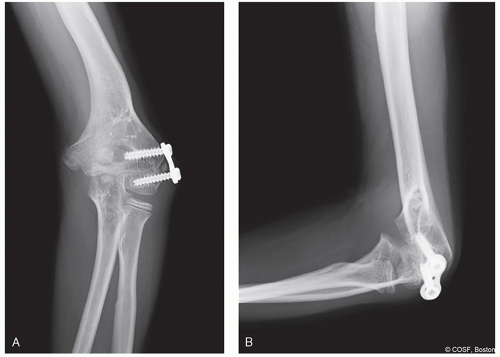

Internal fixation with smooth wires or plates and screws